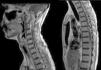

Caso clínicoVarón de 38 años de edad, cocainómano, comienza con cefalea y disminución de la agudeza visual bilateral, interpretado como neuritis óptica, recibió tratamiento con corticoides. Evolucionó con hipoacusia derecha, cuadriparesia nivel T3 y trastornos vesicales. Se realizó RM de cerebro y columna completa con contraste observándose compromiso leptomeníngeo difuso multinodular e imagen seudoquística interhemisférica, asociado a lesiones expansivas intramedulares cérvico-torácicas (figs. 1 y 2). Se estudió con punción lumbar (presión de apertura de 100cmH2O, acelular, glucorraquia normal y proteinorraquia de 107mg/dl), cultivo para gérmenes comunes, micobacterias y hongos, PCR para HSV1-2, VVZ, CMV, VEB y TBC negativos, VDRL en LCR, serología para HIV, micoplasma y toxoplasma negativos. Perfil reumatológico y ECA, sin hallazgos. Inició tratamiento empírico contra toxoplasma y TBC, sin respuesta. Luego de 18 meses de evolución, se realizó biopsia meníngea, arribándose al diagnóstico de pPNET-SNC con t(11;22) (q24;q12). Debido a lo avanzada de su enfermedad, se decidió continuar con medidas paliativas.

RM de columna cervical y columna dorsal. Secuencia sagital T2. Realce meníngeo holomedular y radicular de aspecto nodular que compromete los segmentos C1-C3. Imágenes de aspecto seudoquístico, intradurales extramedulares, que comprometen los niveles C6-C7 y D5-D6, comprimiendo extrínsecamente el cordón medular con dilatación del conducto ependimario.